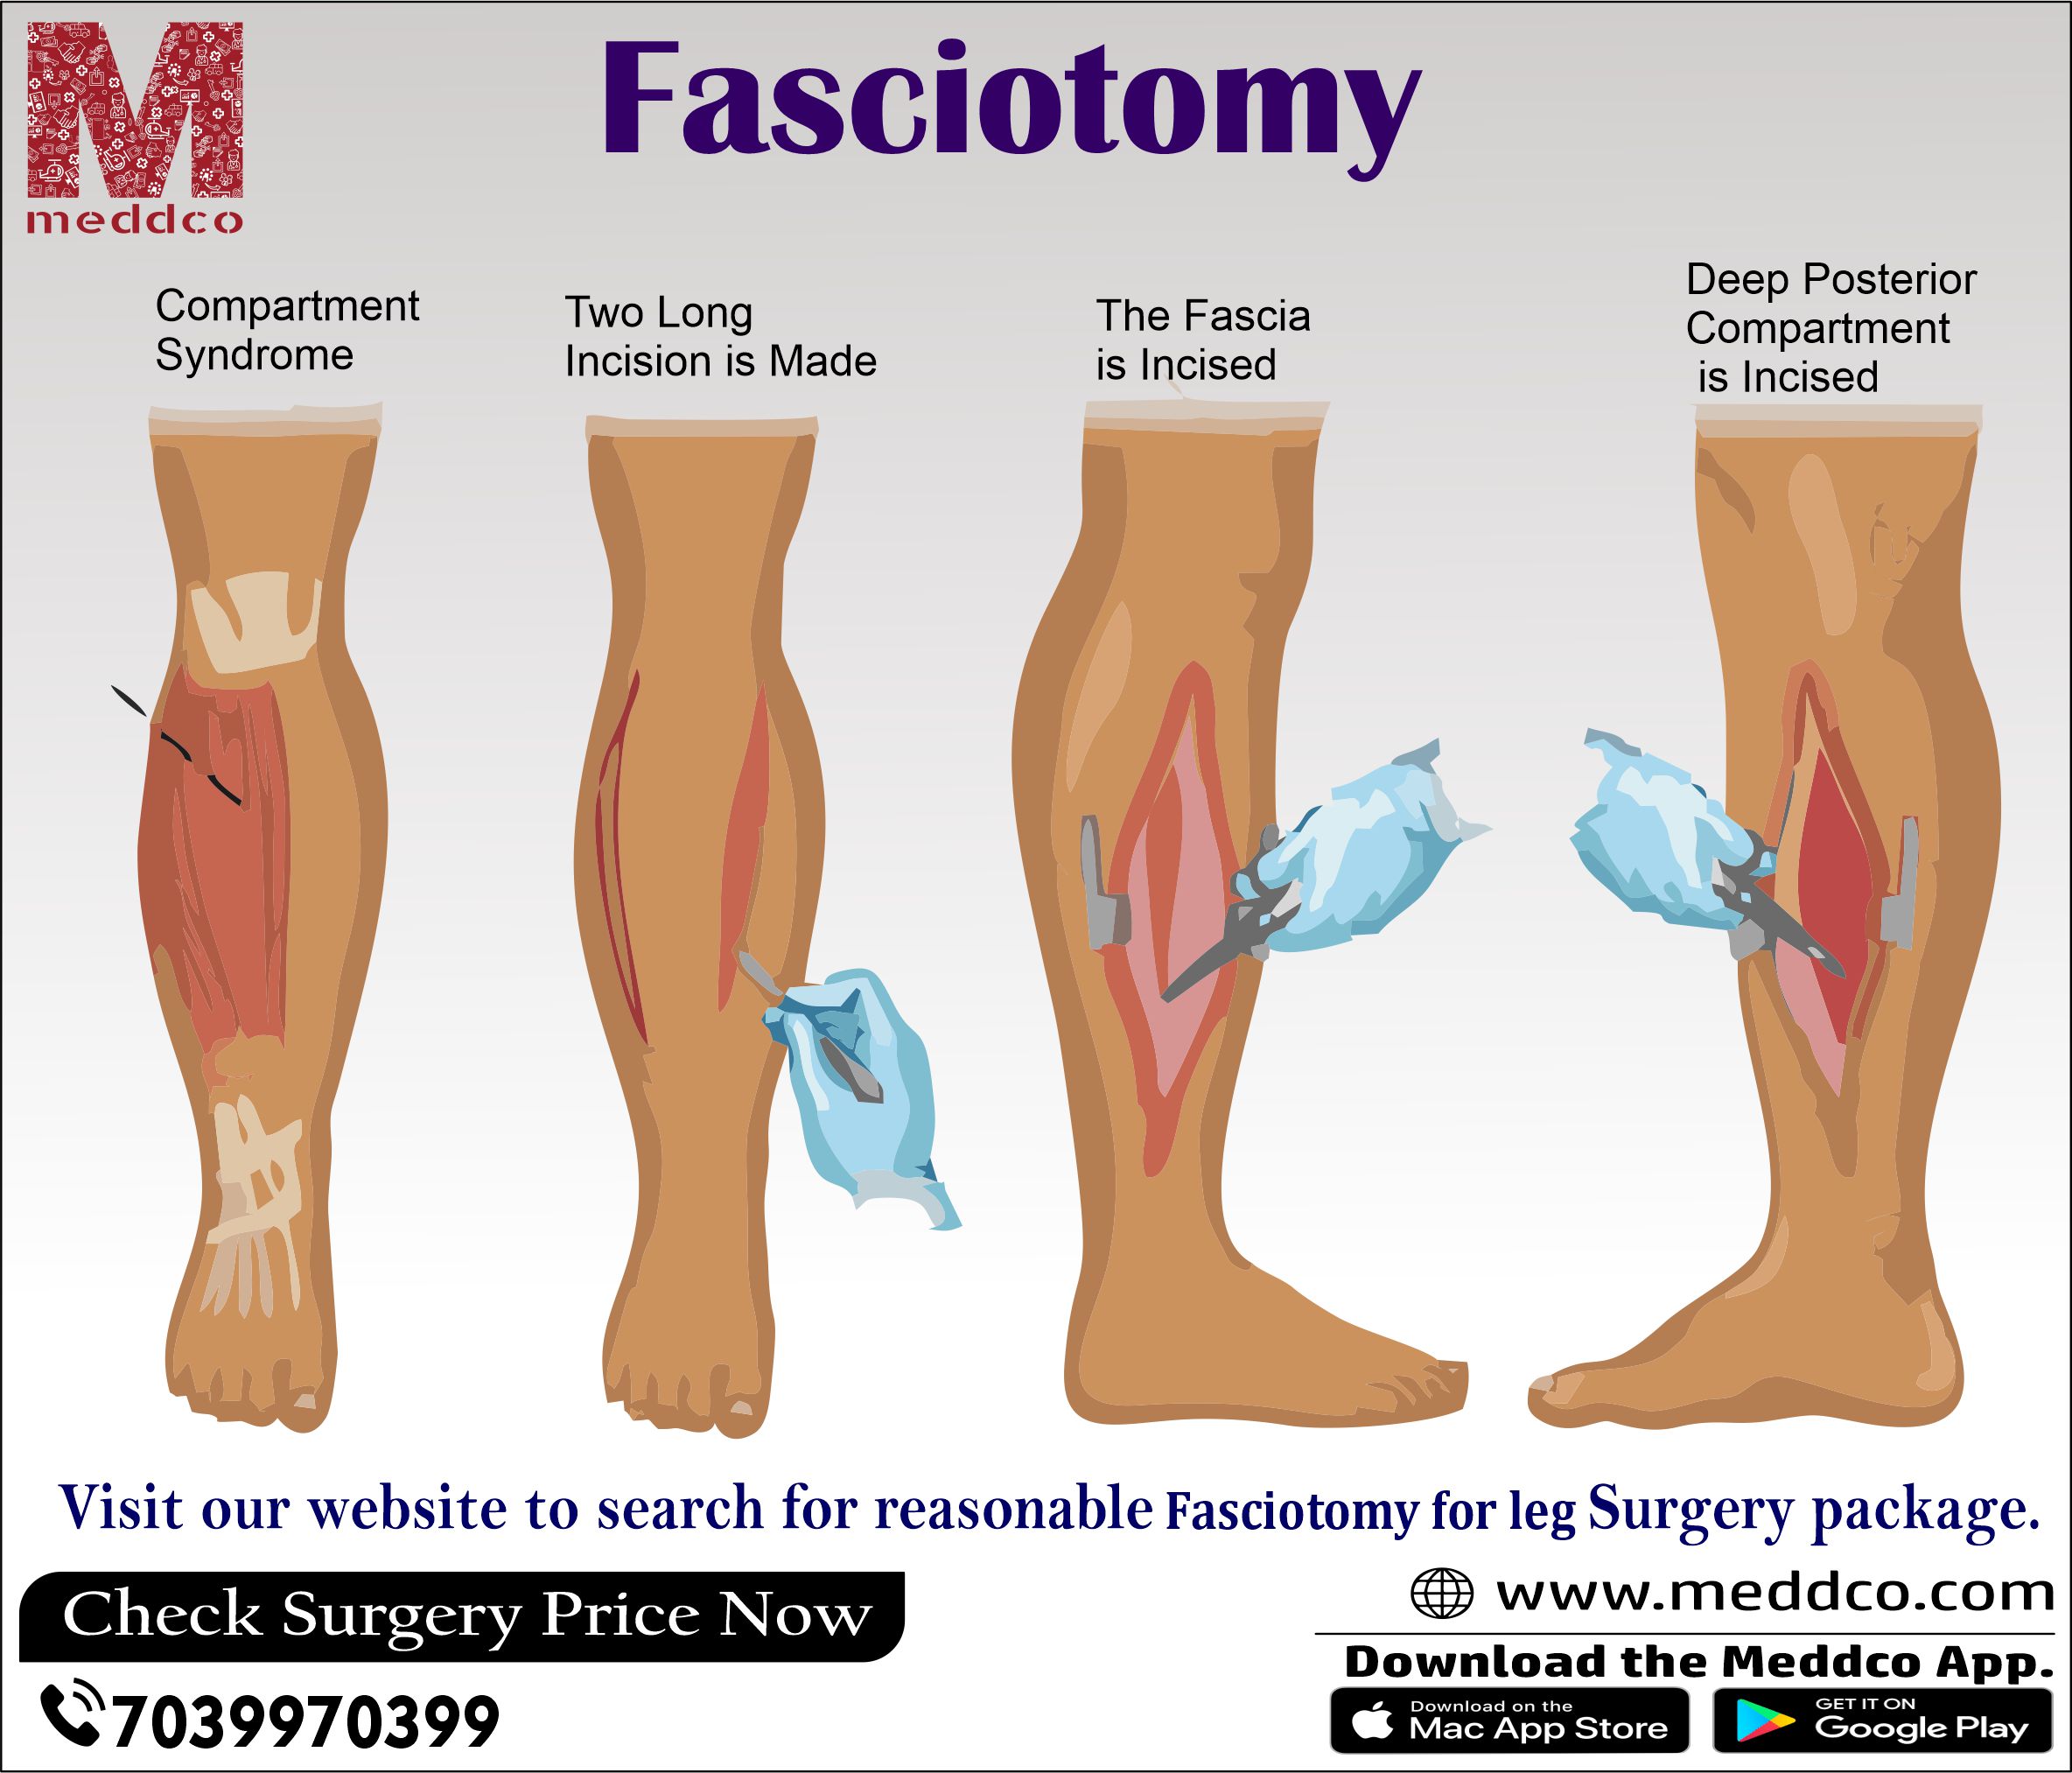

Acute Compartment Syndrome ACS of the lower leg is a time sensitive limb threatening surgical emergency Late findings of ACS can lead to limb amputation contractures paralysis multi organ failure and death

Compartment syndrome is an increase in pressure inside a muscle which restricts blood flow and causes pain If it happens suddenly it can be serious and need treatment as soon as possible

Acute Compartment Syndrome ACS of the lower leg is a time sensitive limb threatening surgical emergency Late findings of ACS can lead to limb amputation contractures paralysis multi organ failure and death

Acute Compartment Syndrome ACS of the lower leg is a time sensitive limb threatening surgical emergency Late findings of ACS can lead to limb amputation contractures paralysis multi organ failure and death

Compartment syndrome is an increase in pressure inside a muscle which restricts blood flow and causes pain If it happens suddenly it can be serious and need treatment as soon as possible

A Guide Through Fasciotomy Surgery